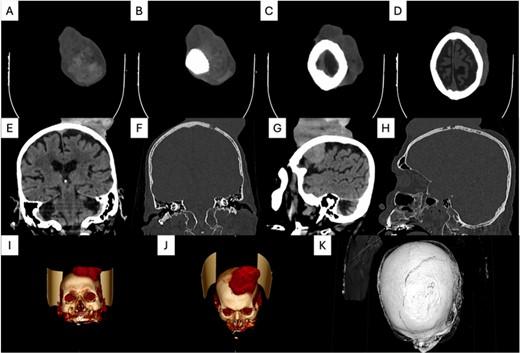

实验室检查显示贫血(血红蛋白为7.4g/dl,铁蛋白水平为12ng/ml,铁结合能力为355mcg/dl)。颈部、胸部和腹部的计算机断层扫描(CT)显示没有转移性病变。头部CT显示弥漫性骨浸润和头皮上方增强的异质性肿块(图2A-K)。肿块对大脑产生了压迫作用。从受影响的皮肤上切下活组织检查。组织病理学检查显示多形性、柱状和长方体细胞,有角蛋白斑点和纤维基质。诊断为混合性基底细胞癌,包括结节和微结节亚型(图3A和B)。

图2 计算机断层扫描结果:头皮上方增强的异质性肿块对大脑产生压迫作用,并伴有弥漫性骨浸润。(A-D)轴位视图;(E和F)冠状视图;(G和H)矢状视图;(I-K)三维重建